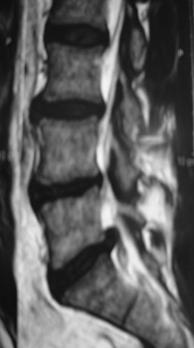

1.- Paciente de 50 años, con HNP L5 – S1, que no respondió a tratamiento conservador, incluyendo antiinflamatorios, fisioterapia y kinesioterapia, por 8 semanas, incluyendo un corticoide peridural por lo que se decidió realizar Nucleotomía Percutánea Automatizada más Apoyo Artroscópico (lo que permite retirar mayor cantidad del tejido herniado).

En este caso se logró una remisión completa del dolor y volvió a trabajar a los 12 días.